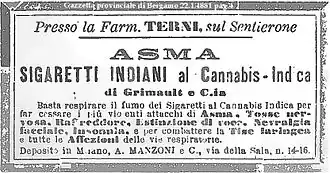

Cannabis (also commonly known as marijuana, weed, pot, etc.) is a plant (Cannabis spp.) that contains a complex of psychoactive substances, the most notable of these being tetrahydrocannabinol (usually shortened to THC). The primary species used as drugs are C. indica and C. sativa. C. ruderalis, which has a low THC content, has been used in some cross-breeding.[2]